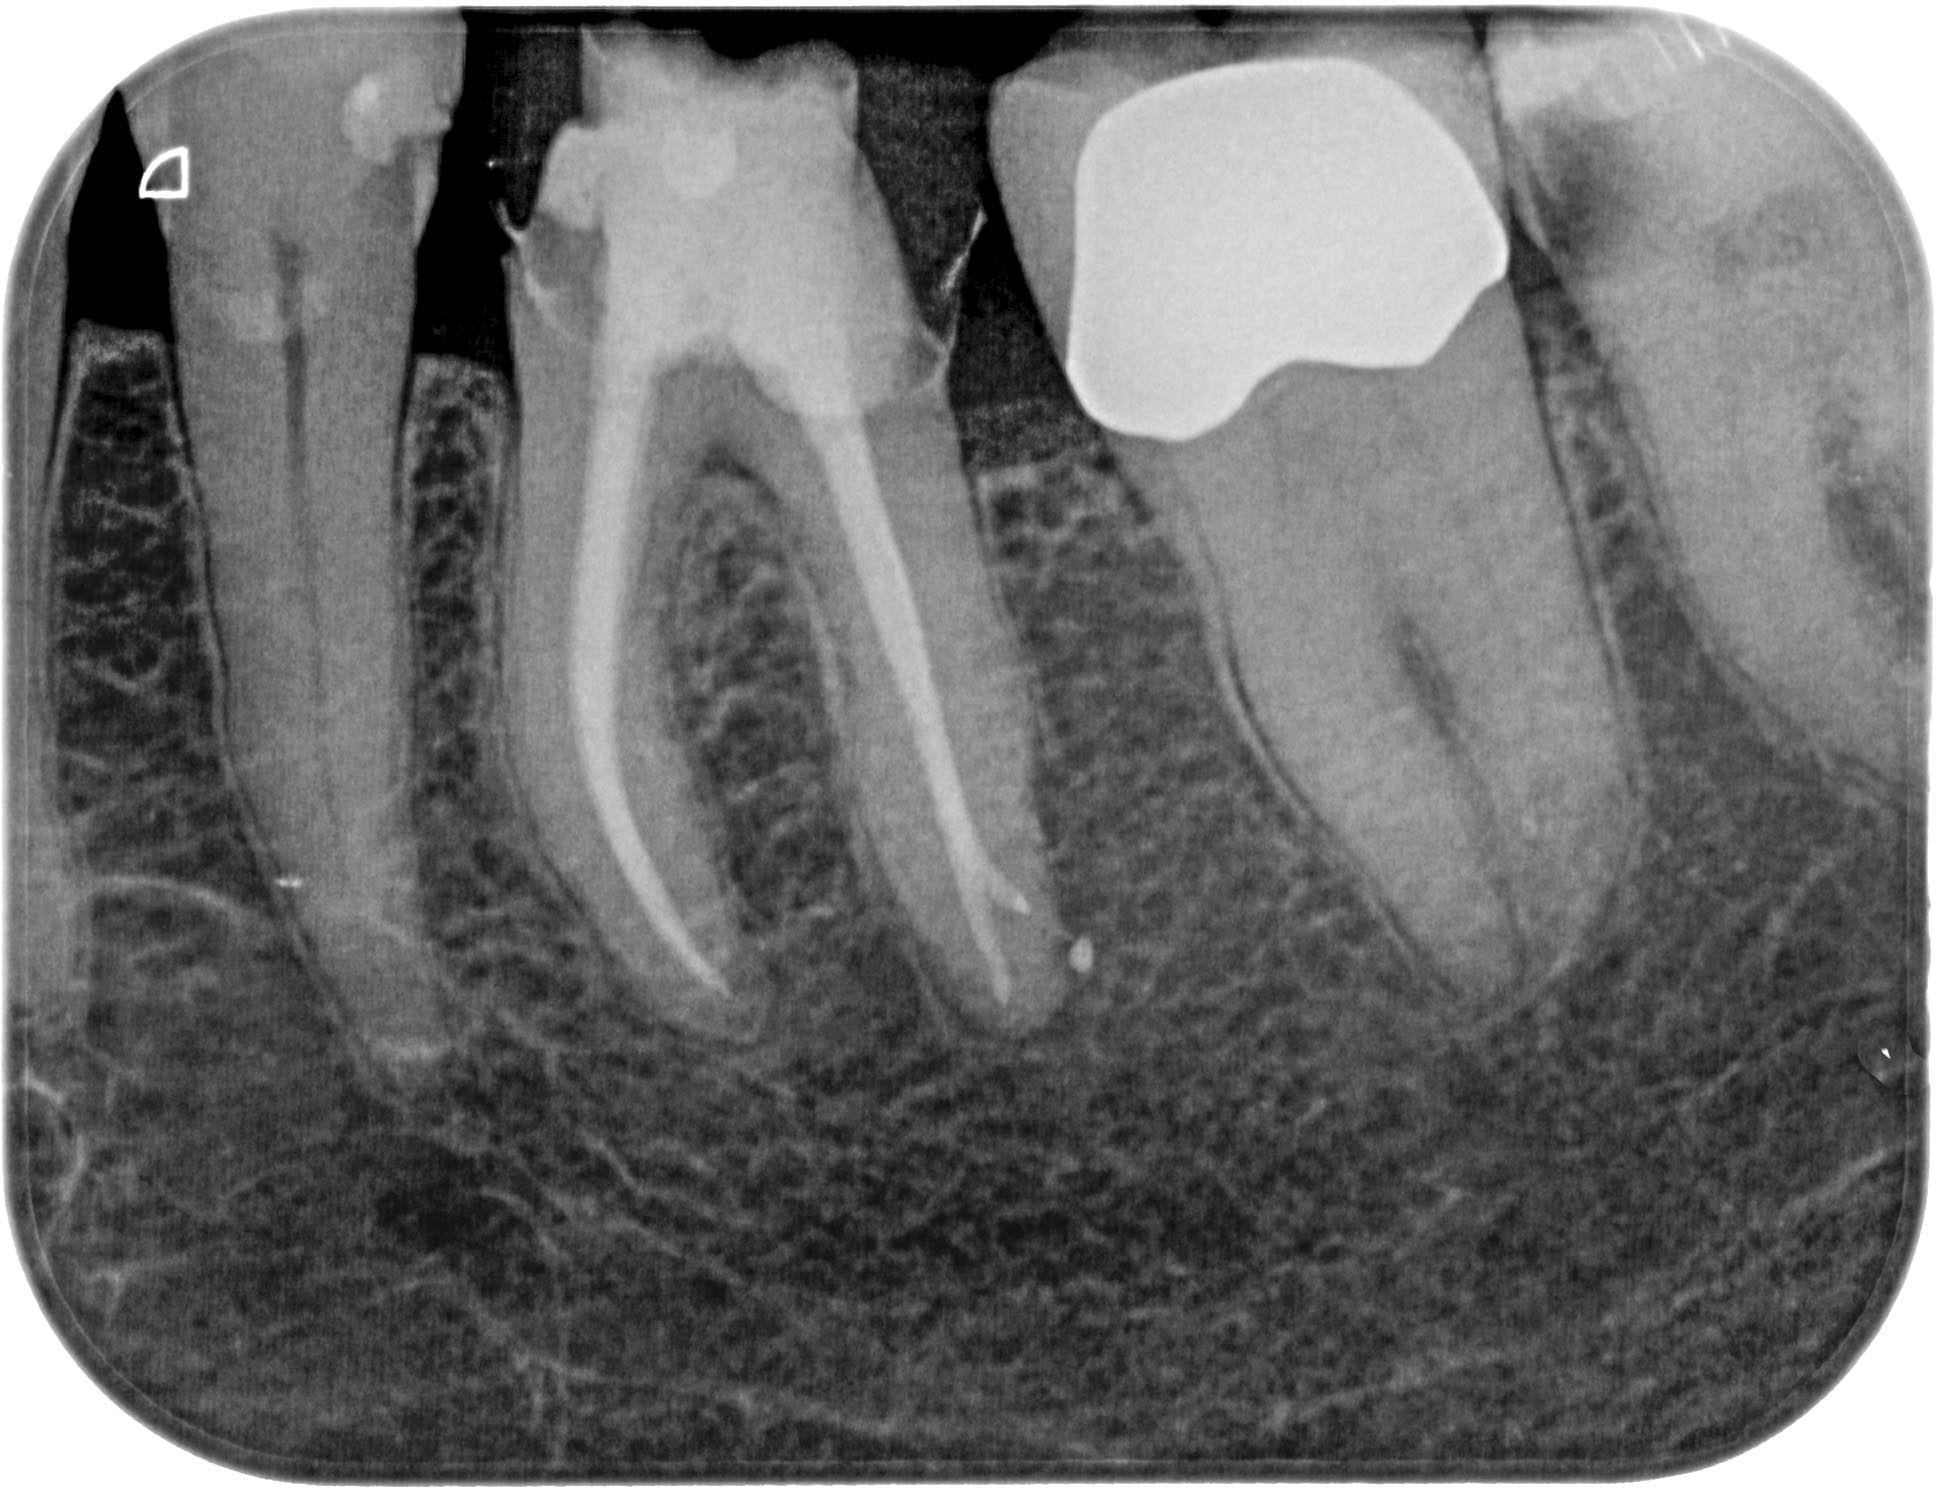

KSKrone6MonatepostWF-1-6 Veröffentlicht 24. September 2015 am 1938 × 1490 in Zuverlässige Endometrie bei Metallkronen – aber auch – Wäre das nicht eine sinnvolle neue Rubrik für WURZELSPITZE ? Zahn 36 6 Monate post WF